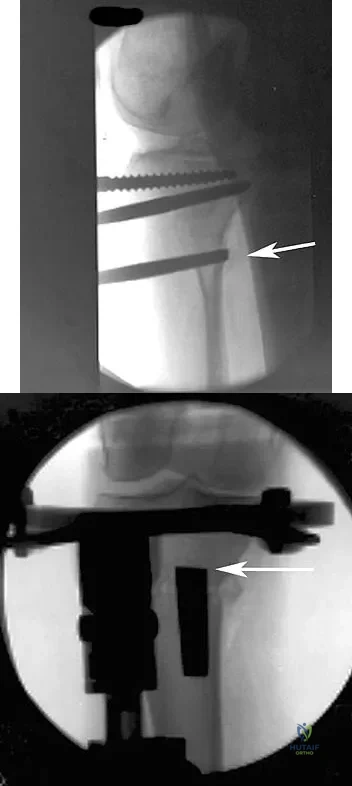

An otherwise healthy 37-year-old man fell off the flatbed of a delivery truck and landed directly on his dominant left hand. Surgical stabilization of a distal radius fracture is performed. An intraoperative radiograph is shown in Figure 22. What is the next most appropriate step in management?